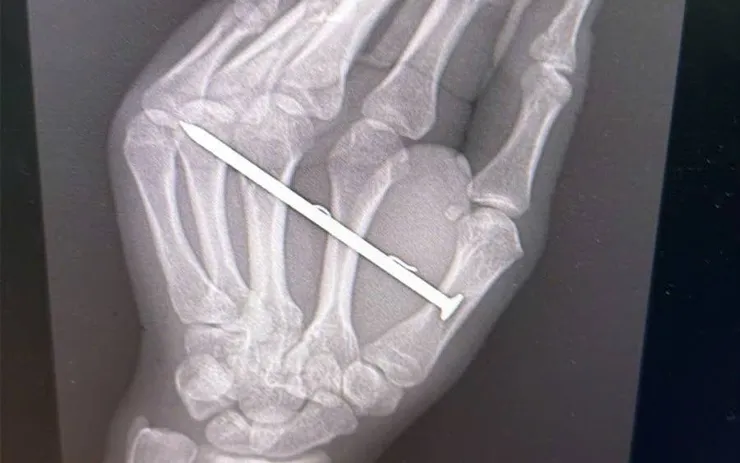

Ngay khi tiếp nhận, ekip Khoa Ngoại Chấn thương chỉnh hình đã tiến hành thăm khám lâm sàng, chụp X-quang xác định chính xác vị trí dị vật. Dị vật sau đó được lấy ra theo đúng kỹ thuật, kết hợp làm sạch vết thương và xử trí tổn thương phần mềm. Người bệnh được theo dõi sát để phòng ngừa nhiễm trùng và các biến chứng ảnh hưởng chức năng bàn tay.